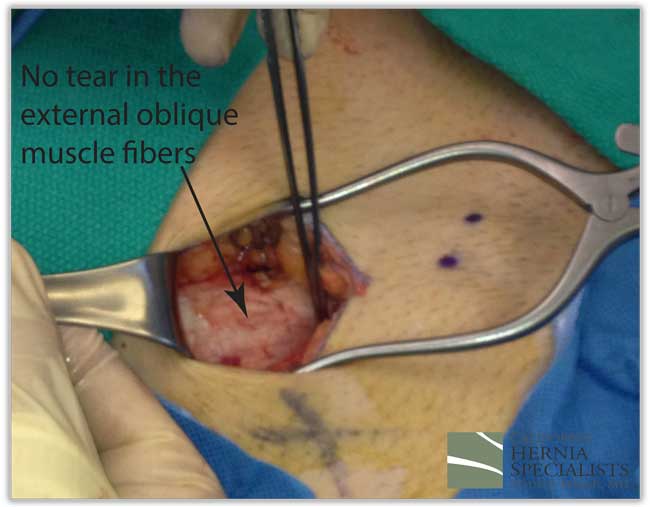

The intra-operative photo above shows an obvious tear in the external oblique, which is the outer layer of muscle in the groin. In the photo, the yellow fat from underneath the muscle is seen between two edges of the white muscle fascia which have torn. The tear was about 4 inches long, and about a 0.5 inch wide. This was repaired with a mesh under the tear, and by closing the tear with sutures.

The photo below shows a normal external oblique which is white throughout with no yellow of fat from underneath and no tear.

On recent follow-up, the patient is having no more pain in his left groin and is back to elite athletic activities on a full time basis.